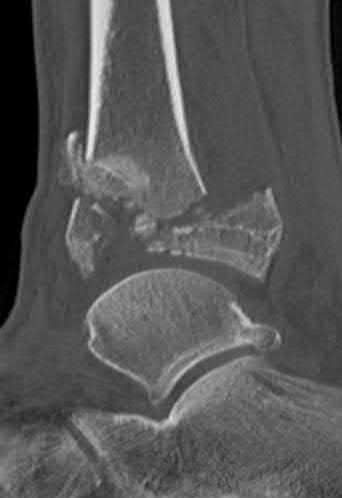

Question 2:

A 28-year-old male sustains a severe hyper-dorsiflexion injury to his ankle in a motor vehicle accident, resulting in a Hawkins Type III talar neck fracture. Which of the following arteries provides the predominant blood supply to the body of the talus, placing it at significant risk for avascular necrosis in this injury?

Correct Answer: Artery of the tarsal canal

Explanation:

The artery of the tarsal canal, which is a branch of the posterior tibial artery, provides the dominant blood supply to the talar body. In a Hawkins Type III fracture (talar neck fracture with subtalar and tibiotalar dislocation), the blood supply from the artery of the tarsal canal, the artery of the sinus tarsi, and capsular vessels are disrupted, leading to an avascular necrosis (AVN) rate approaching 100%.